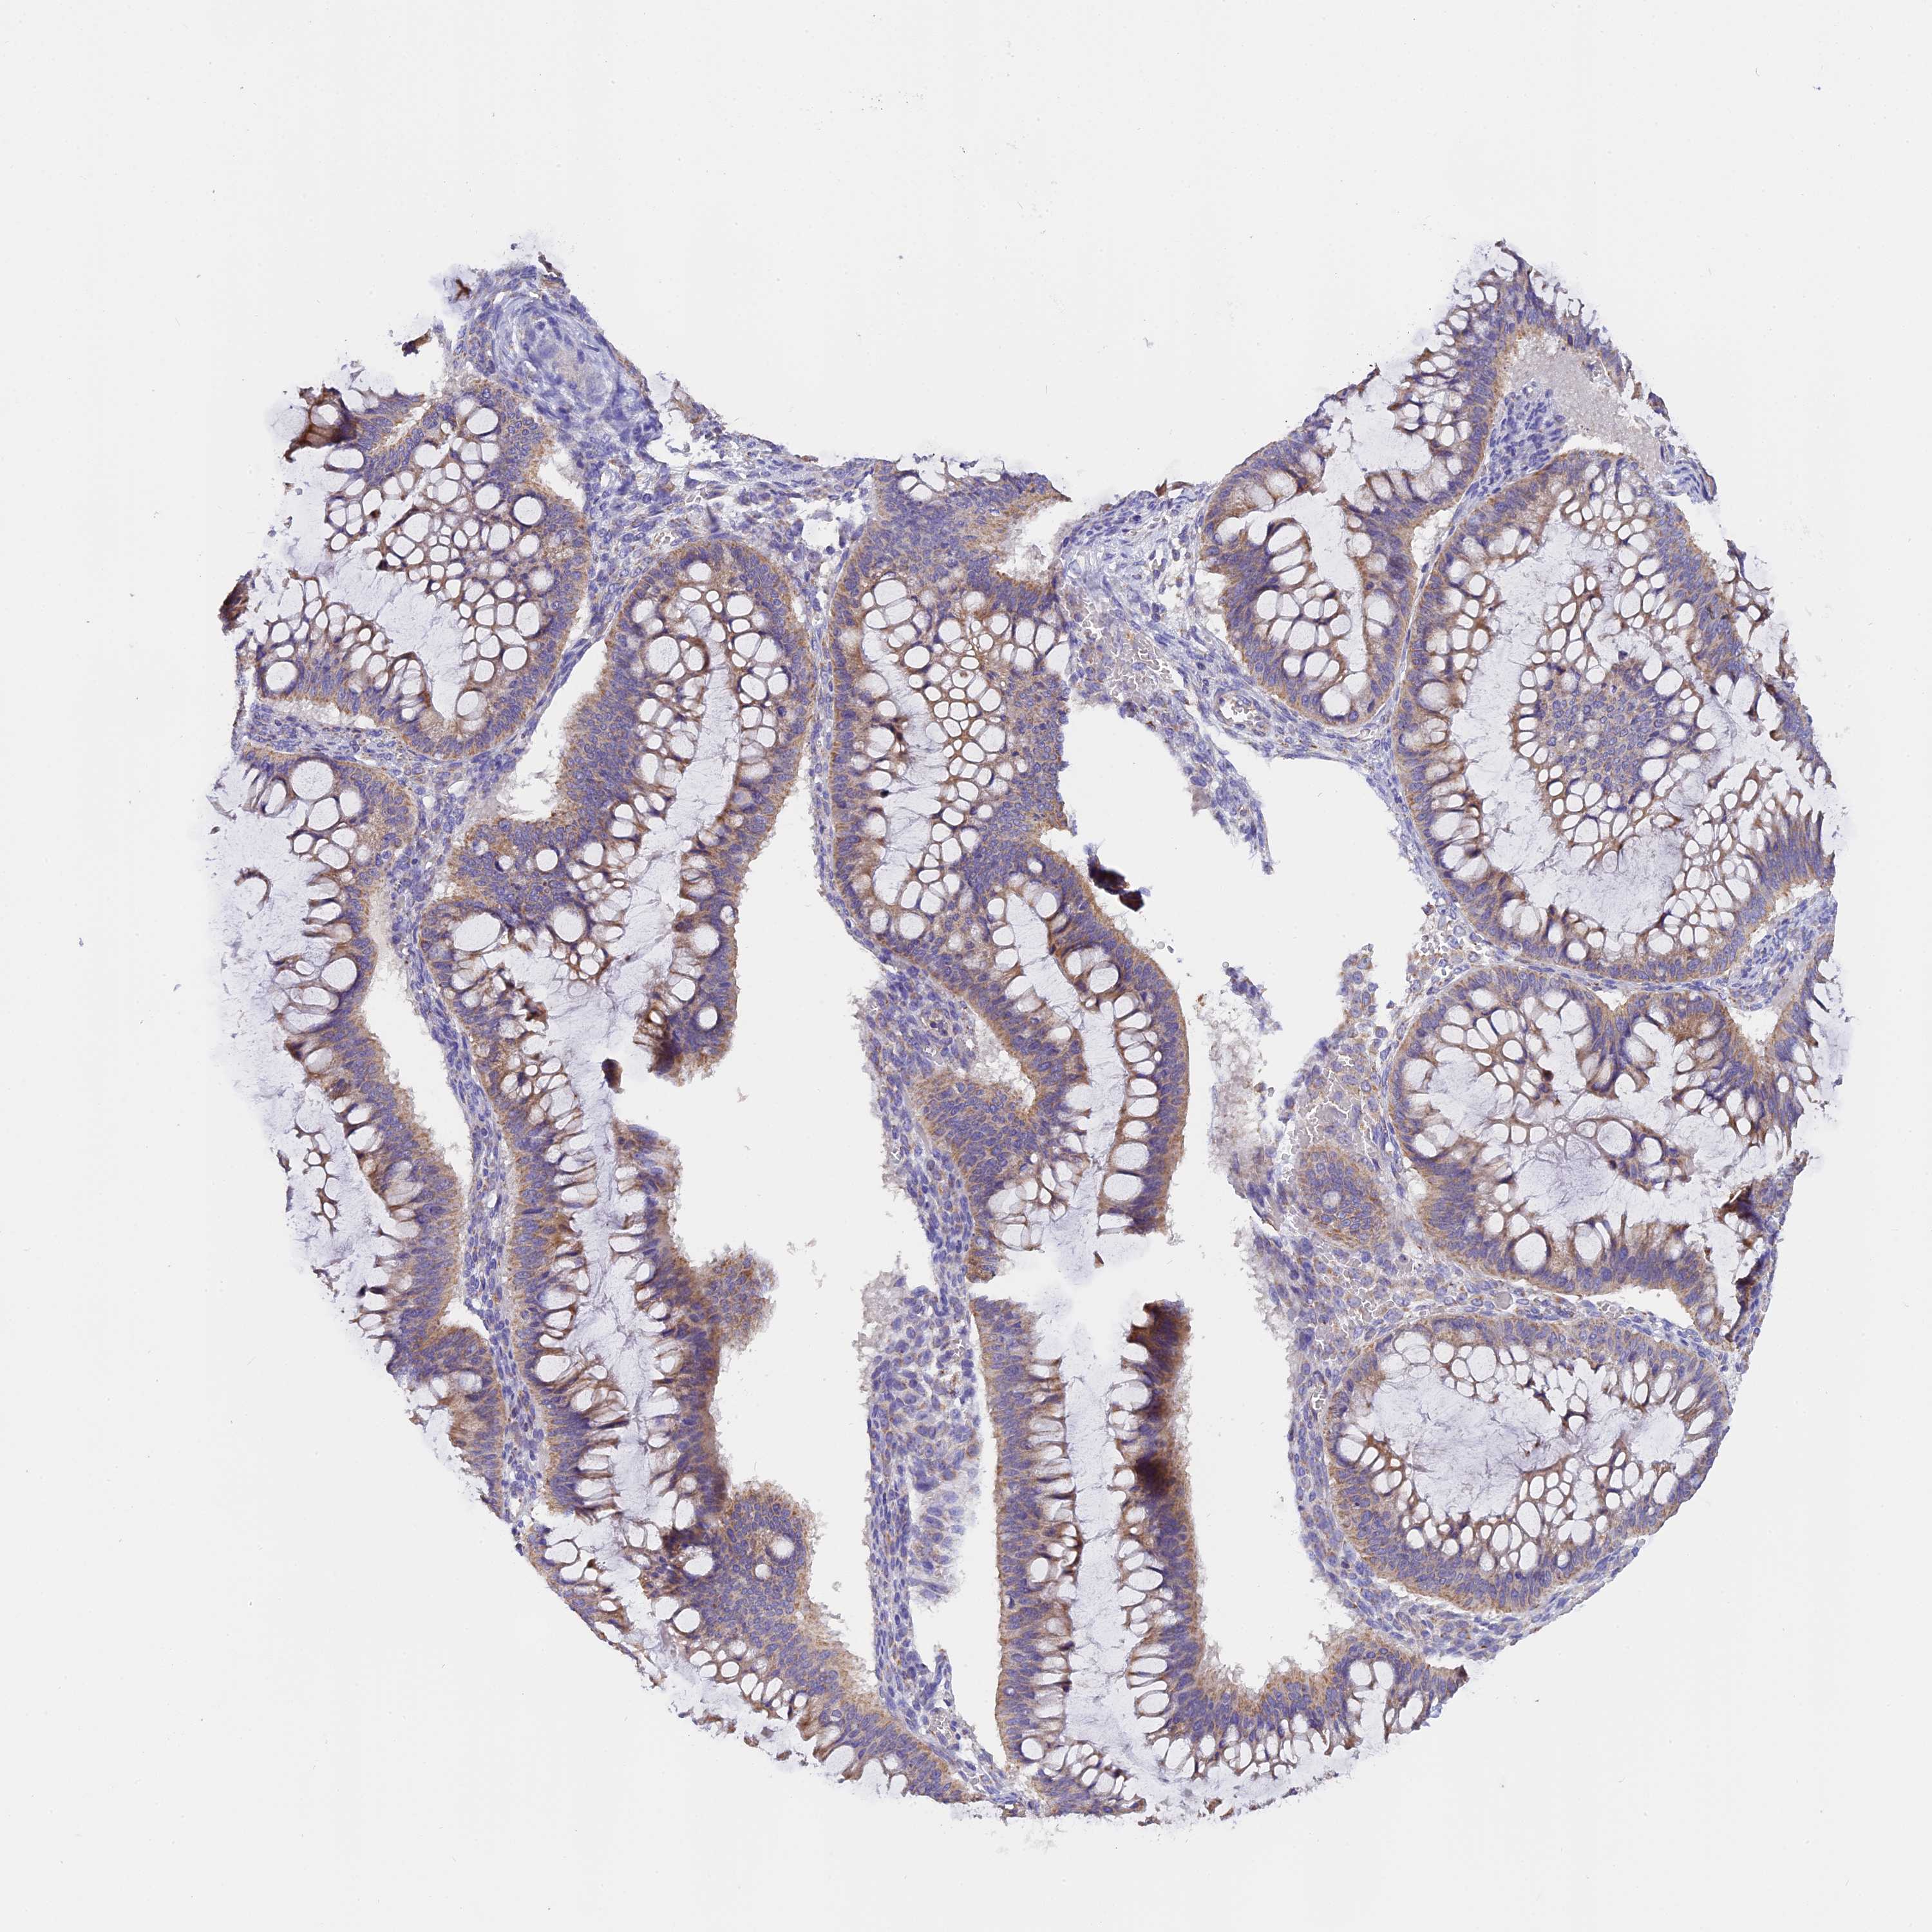

OVARIAN CANCER - Protein expressioni

A mouse-over function shows sample information and annotation data. Click on an image to view it in a full screen mode. Samples can be filtered based on level of antibody staining by selecting one or several of the following categories: high, medium, low and not detected. The assay and annotation is described here.

Note that samples used for immunohistochemistry by the Human Protein Atlas do not correspond to samples in the TCGA dataset.

Antibody stainingi

Antibody staining in the annotated cell types in the current human tissue is reported as not detected, low, medium, or high. This score is based on the staining intensity and fraction of stained cells.